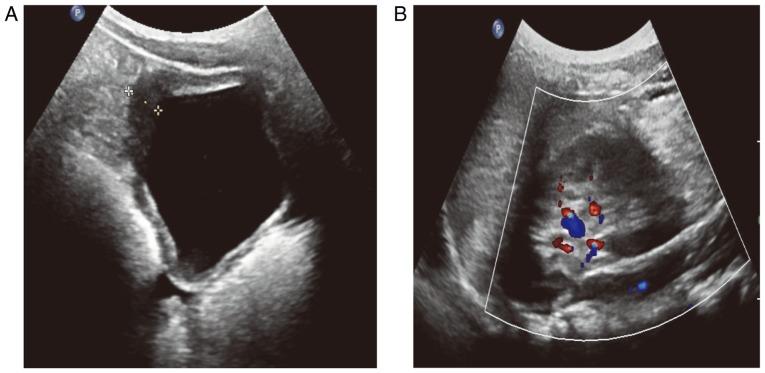

The aim of the present case report was to investigate the clinical features, pathological examination and treatment of eosinophilic cystitis (EC) in children. Two cases of EC were reported and reviewed from January 2016 to March 2017. Case 1 (male; 6 years old) had intermittent hematuria, frequent urination, urgent urination, difficulty in urination and abdominal pain. Case 2 (male; 7 years old) had frequent urination, urgent urination, urinary pain, dysuria and suprapubic pain with no hematuria. One patient had a history of allergies and both patients underwent a cystoscope biopsy. Blood eosinophils were clearly increased and a bone marrow biopsy examination revealed that marrow eosinophils were also increased in both cases. The urine culture results were negative. Ultrasonography and computed tomography revealed uneven thickening of the bladder wall and diffusive mucosal lesions. Cystoscopy revealed that the bladder volume became smaller and the mucosa at the bladder floor and neck was red. Lesions were biopsied through the urethra and the following characteristics were observed: Congestion and edema of the bladder mucosa, infiltration of the blood vessels and eosinophils in the muscular layer, accompanied by focal muscle necrosis. Patient 1 was administered anti-inflammatory and cetirizine hydrochloride treatments, followed by 6 weeks of prednisone dose-reduction therapy. Patient 2 was administered antibiotics and cetirizine hydrochloride. Following 6-month follow-ups, abnormal voiding symptoms had disappeared in each case. Ultrasonography and computed tomography revealed no bladder wall thickening or space-occupying lesions. EC in children is rare and easily misdiagnosed as nonspecific bladder inflammation or bladder occupying lesions. Cystoscopy and biopsy are necessary to diagnose EC and conservative treatments with anti-inflammatory, anti-allergic and cortical hormone nonspecific treatments are suggested.

本病例报告的目的是探讨儿童嗜酸性膀胱炎(EC)的临床特征、病理检查及治疗方法。报告并回顾了2016年1月至2017年3月期间的2例EC病例。病例1(男,6岁)有间歇性血尿、尿频、尿急、排尿困难及腹痛症状。病例2(男,7岁)有尿频、尿急、尿痛、排尿困难及耻骨上疼痛,无血尿症状。1例患者有过敏史,2例患者均接受了膀胱镜活检。两例患者血液嗜酸性粒细胞均明显增多,骨髓活检显示骨髓嗜酸性粒细胞也增多。尿培养结果为阴性。超声和计算机断层扫描显示膀胱壁不均匀增厚及弥漫性黏膜病变。膀胱镜检查显示膀胱容量变小,膀胱底部和颈部黏膜发红。通过尿道对病变进行活检,观察到以下特征:膀胱黏膜充血水肿,肌层血管及嗜酸性粒细胞浸润,伴有局灶性肌肉坏死。患者1接受抗炎及盐酸西替利嗪治疗,随后进行6周的泼尼松减量治疗。患者2接受抗生素及盐酸西替利嗪治疗。经过6个月的随访,两例患者的排尿异常症状均消失。超声和计算机断层扫描显示无膀胱壁增厚或占位性病变。儿童EC较为罕见,易被误诊为非特异性膀胱炎症或膀胱占位性病变。膀胱镜检查及活检对于诊断EC是必要的,建议采用抗炎、抗过敏及皮质激素等非特异性保守治疗方法。